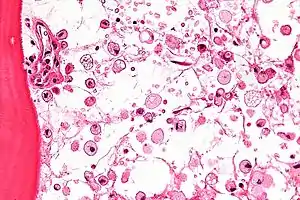

The disease is caused by a defect in housekeeping gene for lysosomal glucocerebrosidase (also known as beta-glucosidase, EC 3.2.1.45, PDB: 1OGS) on the first chromosome (1q22). The enzyme is a 55.6-kilodalton, 497-amino acid-long protein that catalyses the breakdown of glucocerebroside, a cell membrane constituent of red and white blood cells. In Gaucher disease, the enzyme is unable to function correctly and glucocerebroside accumulates. The macrophages that clear these cells are unable to eliminate the waste product, which accumulates in fibrils, and turn into 'Gaucher cells', which appear on light microscopy to resemble crumpled-up paper.[3]

A diagnosis can also be implied by biochemical abnormalities such as high alkaline phosphatase, angiotensin-converting enzyme, and immunoglobulin levels, or by cell analysis showing "crinkled paper" cytoplasm and glycolipid-laden macrophages.